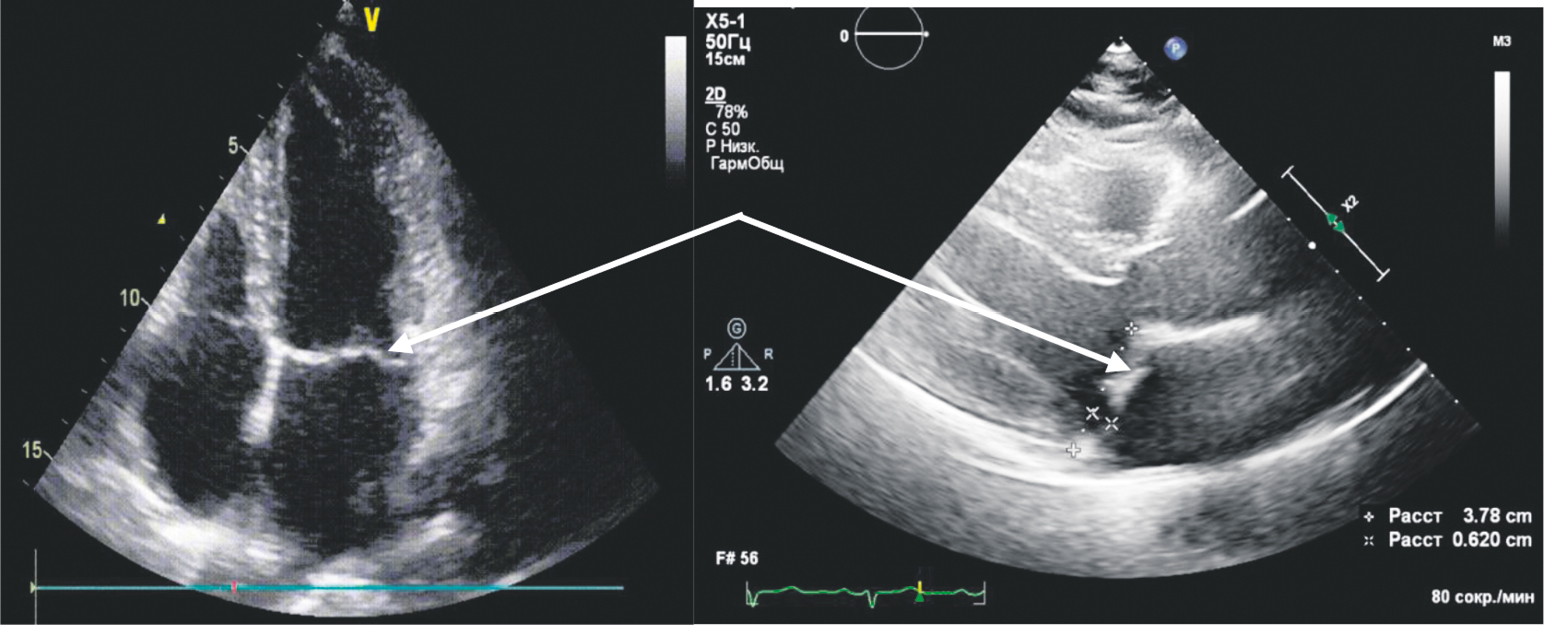

По данным ЭхоКГ (выполнено впервые за все время наблюдения): левый желудочек (ЛЖ) не увеличен, миокард не утолщен, межжелудочовая перегородка 8 мм, задняя стенка ЛЖ 9 мм; локальных нарушений сократимости не выявлено; глобальная сократимость сохранена, фракция выброса ЛЖ 61,2 %. Створки митрального клапана (МК) миксоматозно изменены, пролапс обеих створок МК 2 ст., 8 мм. Регургитация 1 ст., VC 4 мм (рис. 4).

Рис. 4. Эхокардиограмма от 11.10.2023. Стрелками показано пролабирование створок митрального клапана